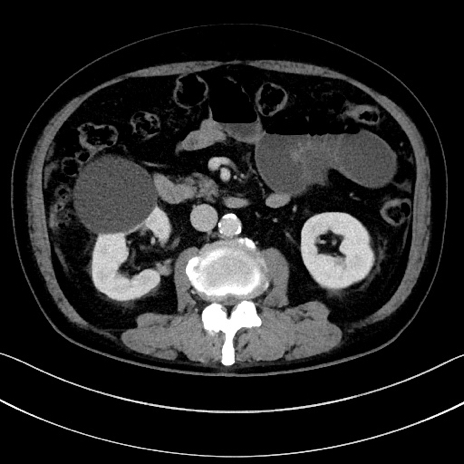

症例15(横断像)

【症例】70歳代男性

【主訴】腹痛

【現病歴】今朝から腹痛あり。全体的に痛い。特に左上の方。排ガスが今日はない。冷や汗が出る。

【既往歴】直腸癌術後

【身体所見】左側腹部〜上腹部に圧痛あり。腹膜刺激症状明らかなではない。軽度反跳痛。左下腹部に術後瘢痕あり。

【データ】WBC 7700、CRP 0.02